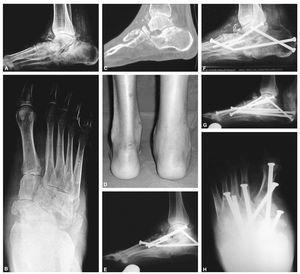

Figura 1. A: varón de 58 años de edad y 2 metros de altura con niveles normales de glucosa, en la radiografía lateral en carga se aprecia un colapso a nivel de la articulación de Lisfranc y astrágalo escafoidea con hundimiento del arco medial. B: proyección oblicua que muestra la desintegración de la articulación de Lisfranc y posteriores, así como una fractura del quinto metatarsiano. C: radiografía lateral en la que se muestra un enclavamiento intramedular desde la cabeza del primer metatarsiano en la columna medial hasta el cuerpo del astrágalo, y enclavamientos anteriores y posteriores. El tornillo en la parte medial del pie aparece roto, pero el paciente no mostró sintomatología, por lo que no precisó revisión. D: una radiografía oblicua muestra el buen alineamiento y consolidación suficiente.